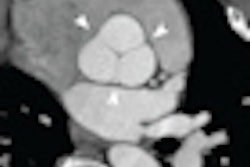

One issue with CCTA is the unclear functional significance of some lesions, and as a result, current guidelines recommend initial evaluation with a noninvasive stress test in most patients, with angiography reserved for patients with positive results, they noted.

CCTA's key selling point is the potential of obtaining anatomic information about the coronary arteries noninvasively, reducing the need for subsequent cardiac testing. A negative CCTA confers a 99% likelihood of not having obstructive coronary artery disease. Still, a CCTA result "is not definitive evidence of obstructive disease," as CCTA is only 88% specific, and additional functional tests are sometimes needed, according to the authors.